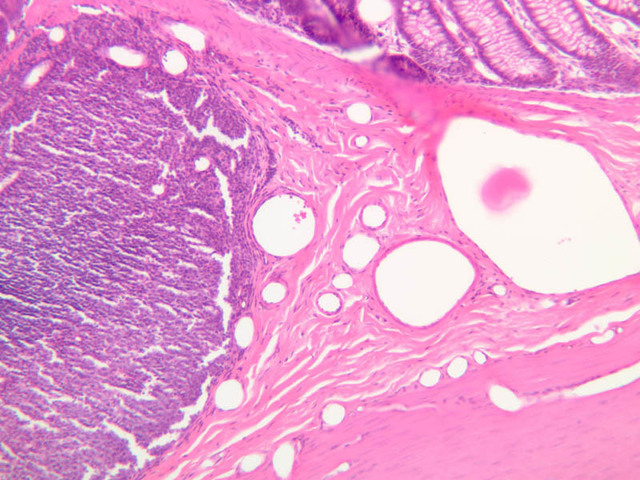

Blood passes from the elastic arteries via arteries of intermediate type into the muscular (distribution) arteries. Locate and examine a muscular artery in slide A-28 (Renal artery & vein, H&E [2.5x, 10x-labeled, 20x, 40x-labeled] [10x-labeled, 20x, 40x]; AF [10x-labeled, 20x, 40x]). Note that the tunica intima is separated from the tunica media by a thick internal elastic membrane which has a scalloped appearance. The tunica media consists of many layers of smooth muscle cells arranged concentrically in a spiral fashion (A-28, H&E [2.5x, 10x-labeled, 20x, 40x] [2.5x, 10x, 20x, 40x, 40x] [2.5x, 10x, 20x]). An external elastic membrane is present, but is thinner and less complete than the internal elastic membrane. The tunica adventitia is about equal in size to the media in this vessel and is more intensely eosinophilic in its staining properties. Note the appearance of small blood vessels in the outer part of the tunica adventitia. You may also be able to see occasional nerve fibers.